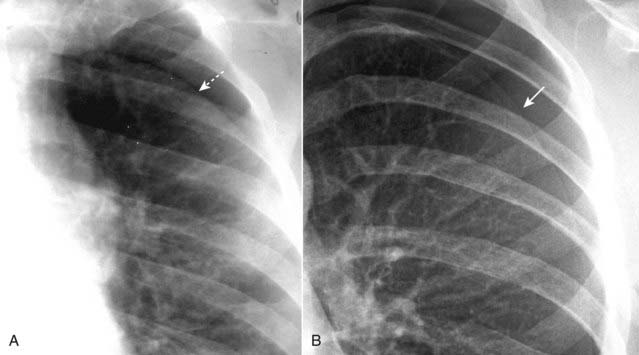

Figure 8-7 Skin fold mimicking a pneumothorax.

When patients lie directly on the radiographic cassette as they might for a portable, supine radiograph, a fold of the patient’s skin may become trapped between the patient’s back and the surface of the cassette. This can produce an edge (dotted white arrow) in the expected position of a pneumothorax, and that edge may parallel the chest wall just as you would expect a pneumothorax to do (A). Unlike the thin, white line of the visceral pleura in a different patient with a pneumothorax (solid white arrow—in B), skin folds produce relatively thick, white bands of density. A skin fold is an edge; the visceral pleura produces a line.